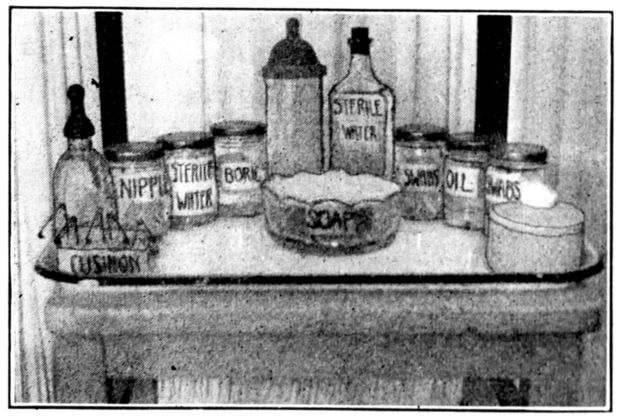

| 146. | Breast tray recommended to expectant mothers by Maternity Centre Association | 417 |

| xxiii147. | Baby’s toilet tray recommended to expectant mothers by Maternity Centre Association | 417 |